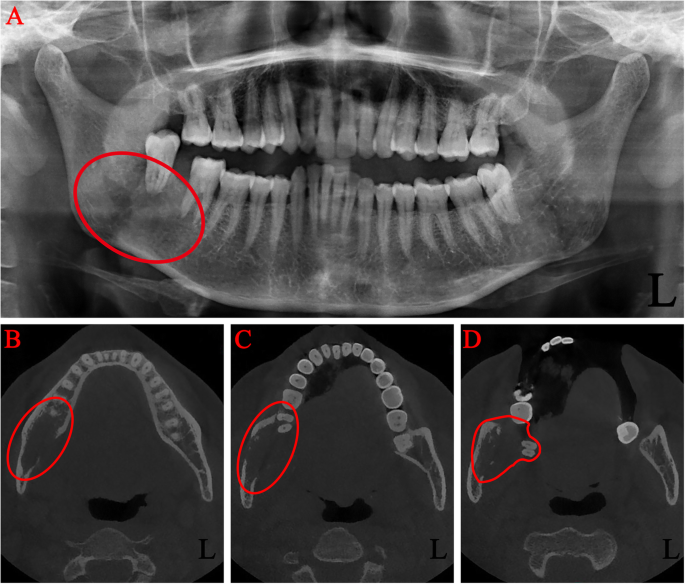

On admission, imaging studies including panoramic radiograph and maxillofacial computed tomography (CT) without contrast were obtained. An ill-defined radiolucent lesion involving the right mandibular angle was noted. The lesion involved the entire bucco-lingual width of the right mandibular angle with extension through the lingual cortex. The right mandibular second and third molars were both super-erupted with a teeth-floating-in-air appearance (Fig. 3a, b, c, d). The outlines of the mandibular canal were obscured by the intraosseous lesion.